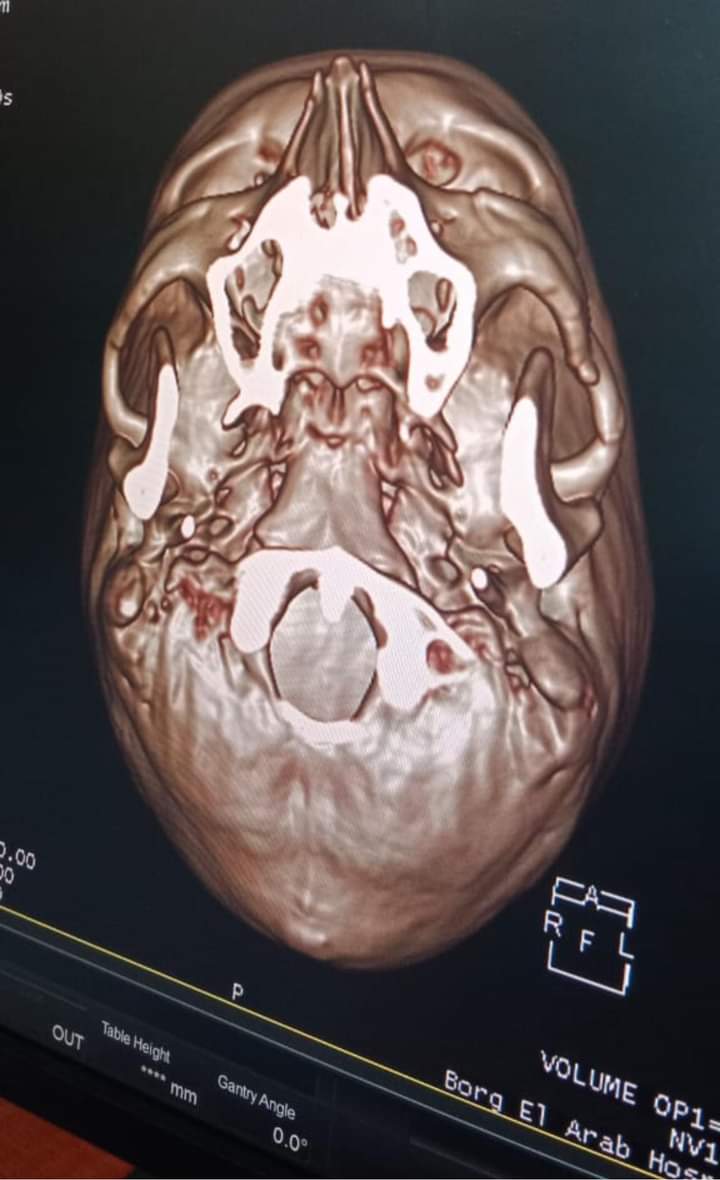

ونجحت مستشفى برج العرب بقيادة دكتور وليد مختار، مدير المستشفي في إجراء التدخل الجراحي لانقاذ حياة شاب يبلغ من العمر 35 سنة، اثر تعرضه لحادث نتج عنه كسر في عظام الجبهة وصل الي المخ وكسر في عظام الوجنه نتج عنه مشكله في فتحه الفم فتحه طبيعه

وأوضح بيان صادر عن مديرية الشؤون الصحية فى الإسكندرية، أن الجراحة تمت بإشراف الدكتورة هبة عارف، مدير عام الطب العلاجي، وأنه تم التنسيق بين قسمي جراحة المخ والأعصاب وجراحه الوجه والفكين لدخول العمليات لرد وإصلاح كسر عظام الجبهة واستئصال كسر منخسف بالجمجمة ورد كسر وخلع بالفك واستعادة فتحة الفم الطبيعية.